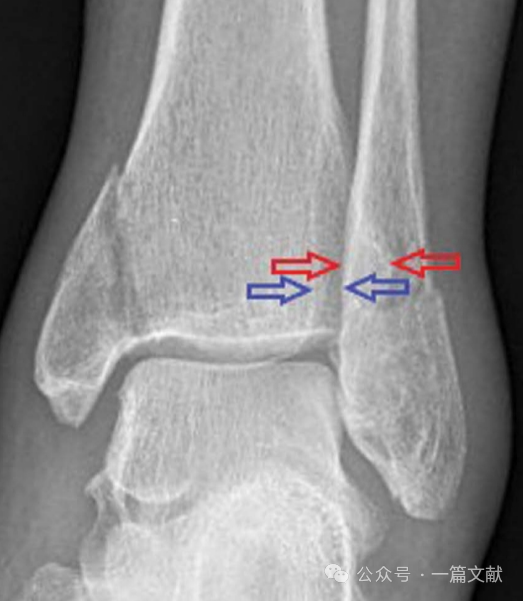

1,透视正位及踝穴位片,来观察胫腓骨重叠距离如下图红色箭头之间距,若标准正位片上此距离小于6mm,或踝穴位片小于1mm则考虑下胫腓不稳定。或者于关节面以上1cm处观察胫腓骨间隙如下图蓝色箭头之间距,与健侧相比,若增加2mm以上,则考虑下胫腓不稳定。